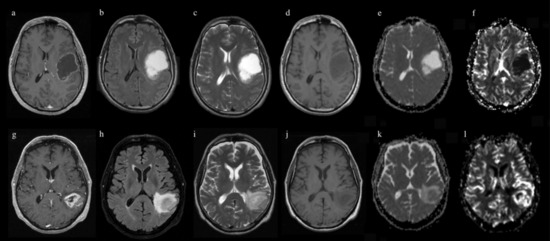

2. Materials and Methods